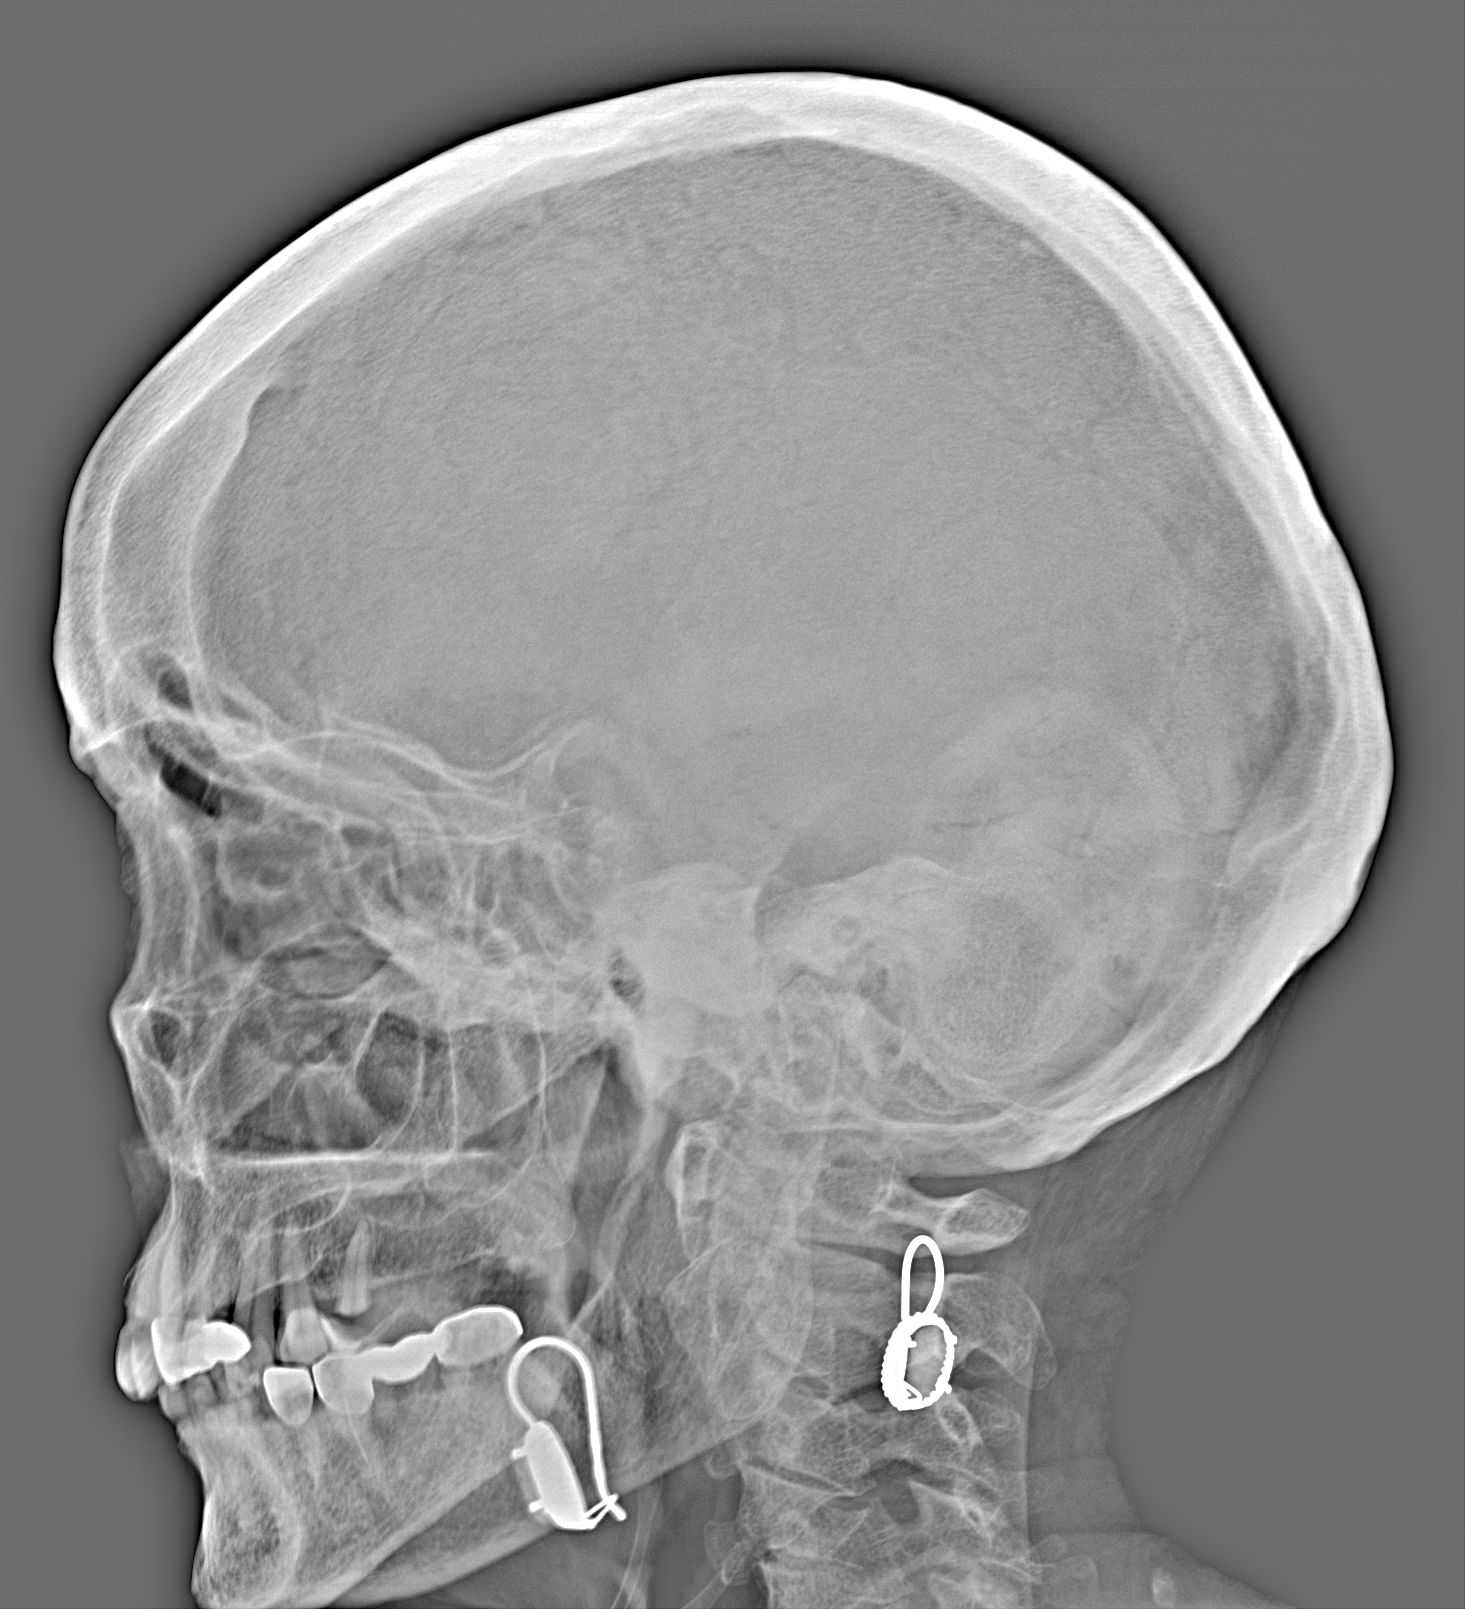

Рентгенограммы

Рентген на дому: по вашему адресу приезжает врач-рентгенолог, травматолог-ортопед с мобильным рентгеновским аппаратом, проводит диагностику травмы или заболевания, делает необходимые рентгенограммы, дает рекомендации по дальнейшему лечению. Получить качественные снимки в домашних условиях возможно благодаря уникальной методике, разработанной МосРентген Центром для института  Склифосовского